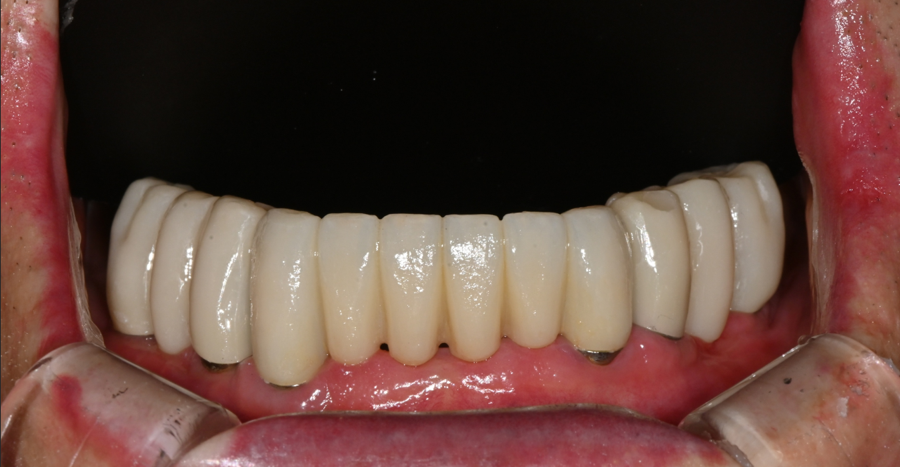

Final OVZERO veneer placement (OVZERO)

The final veneers completed in the lab were made with a subtle translucency like natural light,

a texture close to natural teeth,

and a shape that naturally matched the senior patient’s lip line.

After placement, the patient looked in the mirror

and smiled brightly, saying,

“I think I look 10 years younger.”

In particular, once the front teeth became brighter,

the entire face took on a softer and brighter impression.